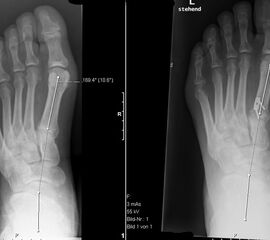

Peroneus longus auf brevis Transfer (Abb. 4 und 5, Video 3)

• Plantarflektiertes Metatarsale I (lateraler Talo-MT I Winkel mehr als 10°) und schwacher M. peroneus brevis (lateraler Rückfuβ-Instabilität).

Die meisten neurologischen Hohlfüsse weisen einen funktionalen M. peroneus longus bei schwachen M. peronaeus brevis und schwachen M. tibialis anterior auf 11. Der Zug des M. peroneus longus nach plantar trägt zum überhöhten medialen Längsgewölbe und sekundär zum Rückfuβ varus bei. Hinsichtlich Reduktion des plantarflektierten Metatarsale I und Kräftigung der Rückfuβ-Eversion mit Stabilisierung des lateralen Rückfuβes ist der Transfer ausgesprochen effektiv.

Dorsalflektierende Osteotomien des medialen Mittelfuβes (Abb. 6 – 9, Video 4)

• Erhöhter lateraler Talo-Metatarsale I Winkel (Meary-Winkel) als Ausdruck des plantarflektierten medialen Mittelfuβes, insbesondere im "forefoot driven hindfoot varus" (positiver Coleman block Test).

Generell wird die dorsalflektierende MT I Osteotomie (Abb. 6 und 7) nicht isoliert ausgeführt, sondern ist Teil der gesamten Hohlfuβ-Korrektur. Beim absolut flexiblen Hohlfuβ ist sie gelegentlich zusammen mit einem Peroneus longus auf brevis oder einem Release der Plantarfaszie ausreichend. Diese Osteotomie ist einfach durchzuführen und hat eine geringe Pseudarthroserate.

Eine ähnliche dorsalflektierende Osteotomie des Os cuneiforme mediale (reversed Cotton Osteotomie, Abb. 8 und 9), ebenfalls mit Entnahme eines dorsal basierten Knochenkeils, ist effektiver im Ausmass der Korrektur, jedoch oftmals wegen der Insertion des kräftigen Lisfranc-Ligaments nur schwierig zu schliessen.